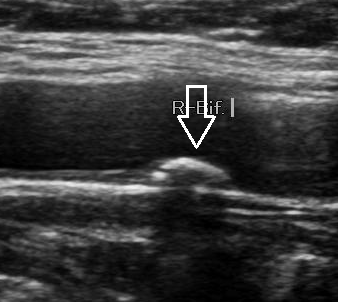

5. 혈관 노화 지표

- 내중막 두께(IMT) 측정으로 혈관 노화 정도를 정량화할 수 있습니다.

- 초음파 검사 시행

- 침대에 누워 목 양쪽에 초음파 탐촉자(probe)를 대고 관찰